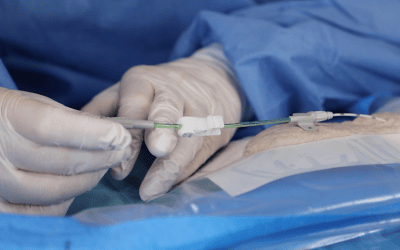

3. Acceso por la vena subclavia en adultos

La vía subclavia en comparación la vía yugular es más funcional y estética evitando muchas de las complicaciones relacionadas con la punción a ciegas.

Además, no es necesario tunelizar, es un abordaje más cómodo et rápido.

Hoy en día, nuestra vía de abordaje de elección era la vena subclavia en el surco deltopectoral, lo cual permite una gran discreción para los pacientes (respeto del escote). Colocamos el 99% de nuestros puertos con este abordaje.

Se han realizado alrededor de 10.000 procedimientos en nuestro instituto desde 2007, con esta técnica y con esta técnica no hubo casos de neumotórax, punción arterial o síndrome de Pinch off.

En este caso, se crea el bolsillo de un tamaño ajustado al tamaño de la cámara ya que no se sutura a los tejidos subcutáneos. Eso permite que no se de la vuelta y evita las grandes dificultades que existen a la hora de la retirada cuando se sutura.

Se punciona la vena en el fondo del bolsillo: de esta manera el catéter tiene un recorrido más fisiológico y evitamos los posibles curvas o acodamientos que pueden crearse cuando la vena se punciona desde otro lugar.